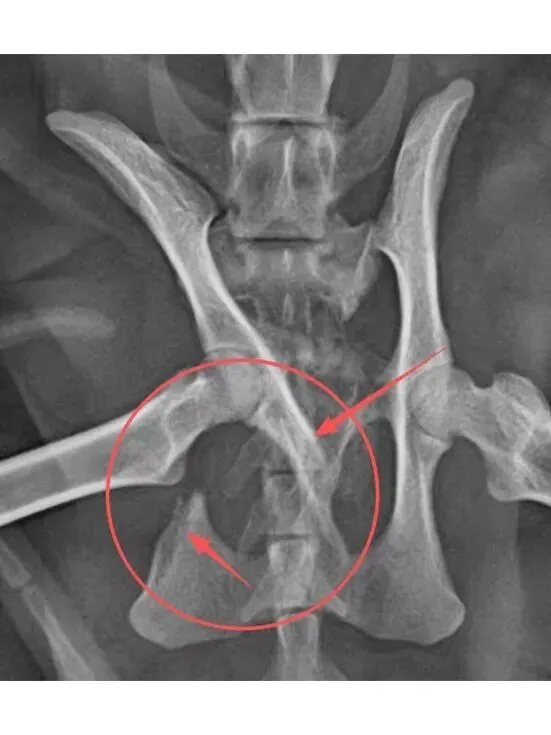

盆骨X光片:盆骨粉碎性骨折,因十号的生化血常规和SAA指标达标,于是准备12号进行手术。

由于只因应激导致心脏骤停的情况较为罕见,医生在事后继续完成未进行的心超检查,发现鸡腿极有可能是因为原本存在的气胸漏液渗到肺部,从而导致肺部受压、供氧不足,加上因环境变化产生的应激,最终引发心脏骤停。以上情况表明,鸡腿极有可能在10号或者10号之前就存在肺部损伤,类似外伤引起肺挫伤。